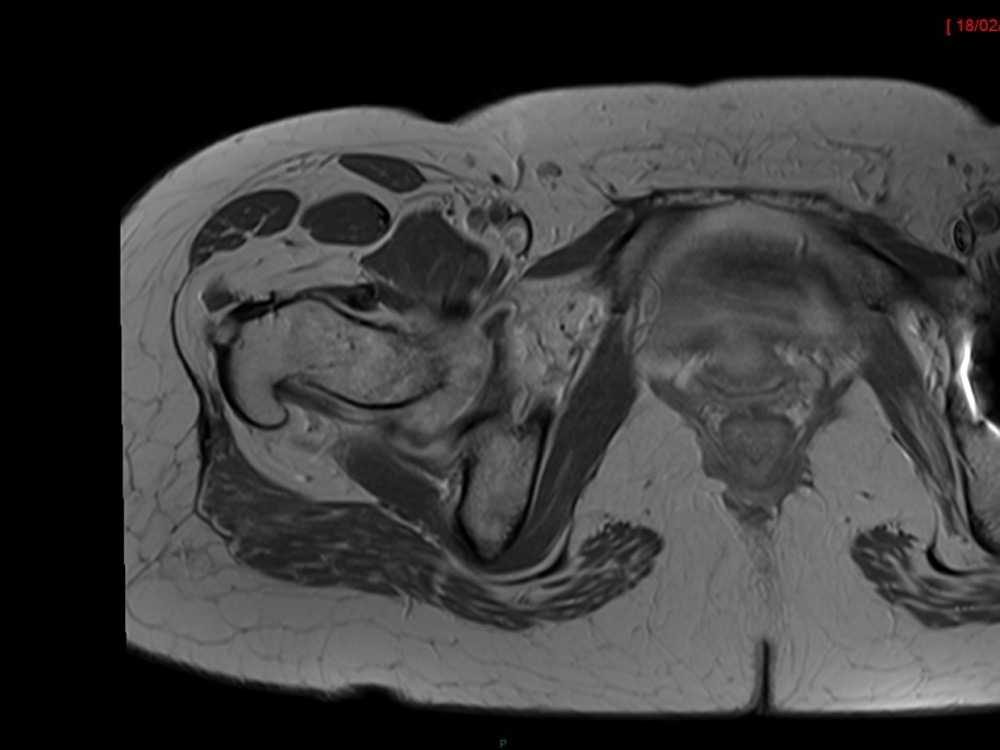

Aboudaram / Burns 11/01/2023